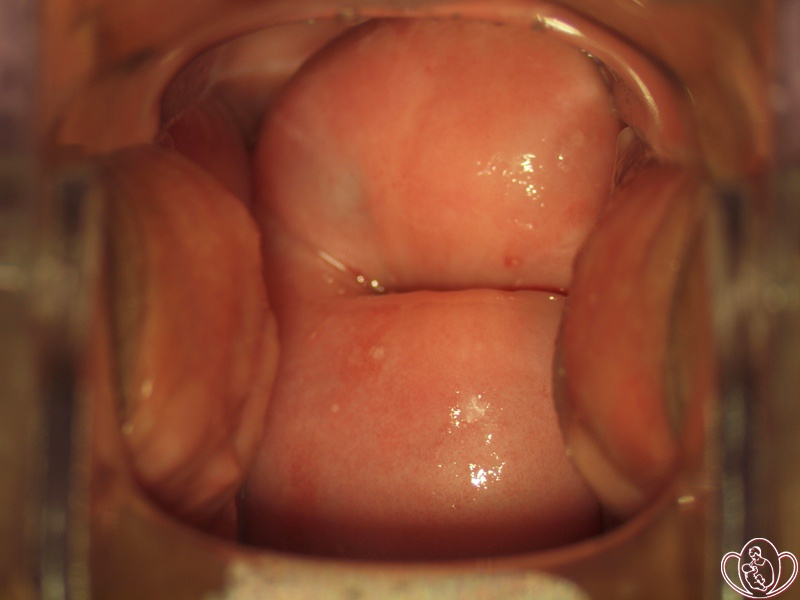

Фото шейки матки . Шейка после традиционного электрохирургического лечения («прижигания») в 2010 году . Фото полипа . Гранулематозный полип культи влагалища после экстирпации матки (полного удаления матки) .